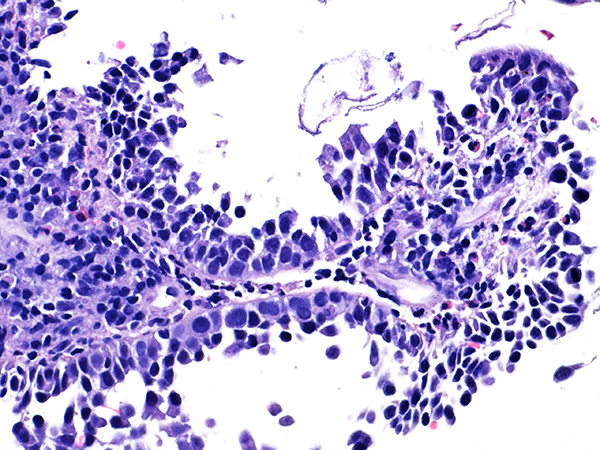

Case 1

Area 1 - Soft Bx CIN 2 40x - High Power |